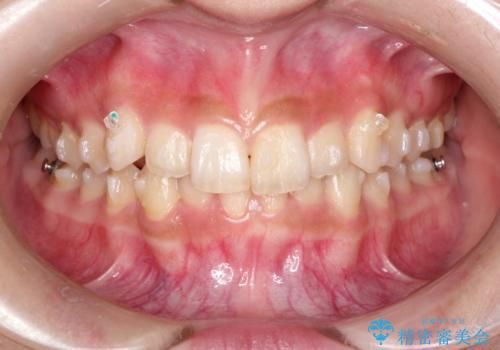

- インビザライン

インビザラインを使用して矯正する計画としました。

ディープバイトの場合、ワイヤー装置の装着が難しいことがあります。

インビザラインではかみ合わせに左右されず装着できるメリットがあり、ワイヤーに比べインビザラインの方が治療しやすい場合もあります。